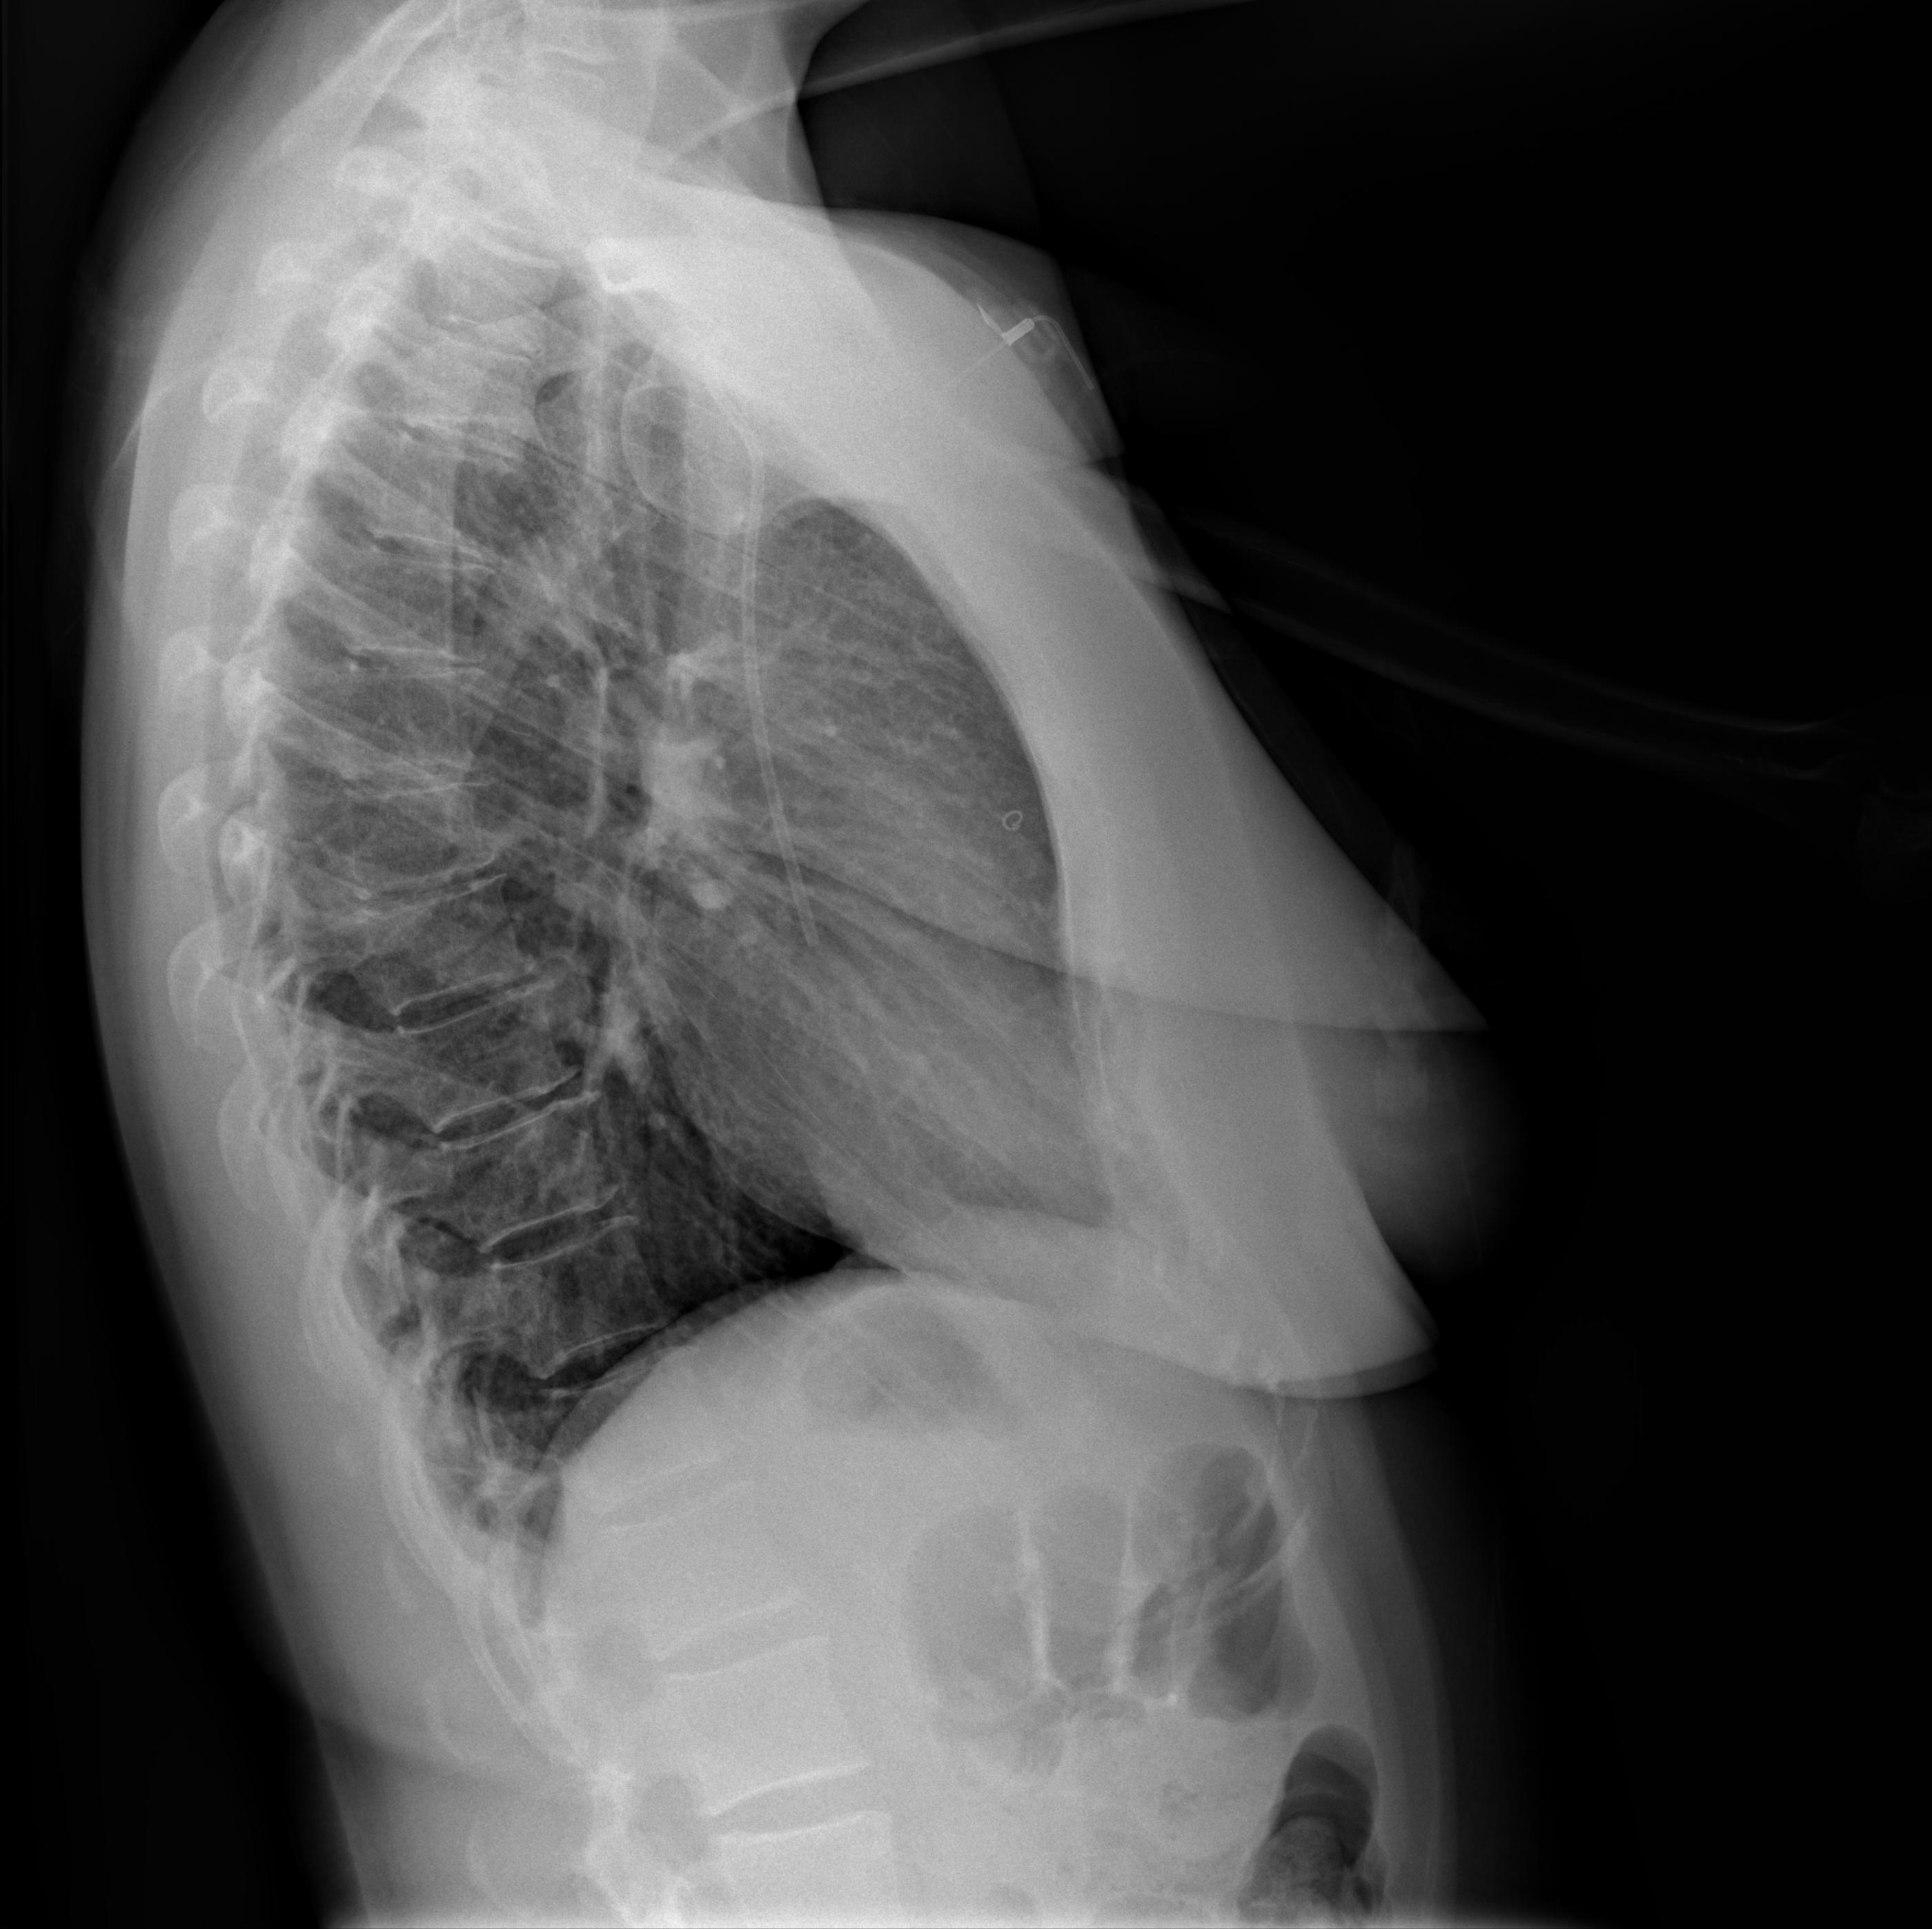

I had a short break of a few days, and the medical checkups resumed on October 27th, when a few things happened. The first of these things was a chest radiology exam, which showed that no pulmonary lesions were present or suspected. Another piece of the puzzle falling into place.

I included here the two x-ray images, along with a recap of the protocol they used for the exam. I will be honest, I don’t understand it (all), but I couldn’t help but thinking that this is data that plays a crucial role, too: a different protocol might have shown things differently? more of it, less of it?

Chemotherapy day (finally) arrived: the sooner I started, the better, obviously. Not sure what happened on the day, but I fainted while getting ready. The pain from the port surgery, the tiredness, the stress of it all, I just went down on my face. My oncologist suspected a pneumothorax (a collection of air outside the lung but within the pleural cavity) so I was sent to radiology for some x-rays.

They checked my lungs during inspiration (first image) and expiration (second image): you can clearly see Portia with the catheter getting into my subclavian vein.

Luckly enough, I didn’t have a pneumothorax, so we went ahead with chemotherapy.